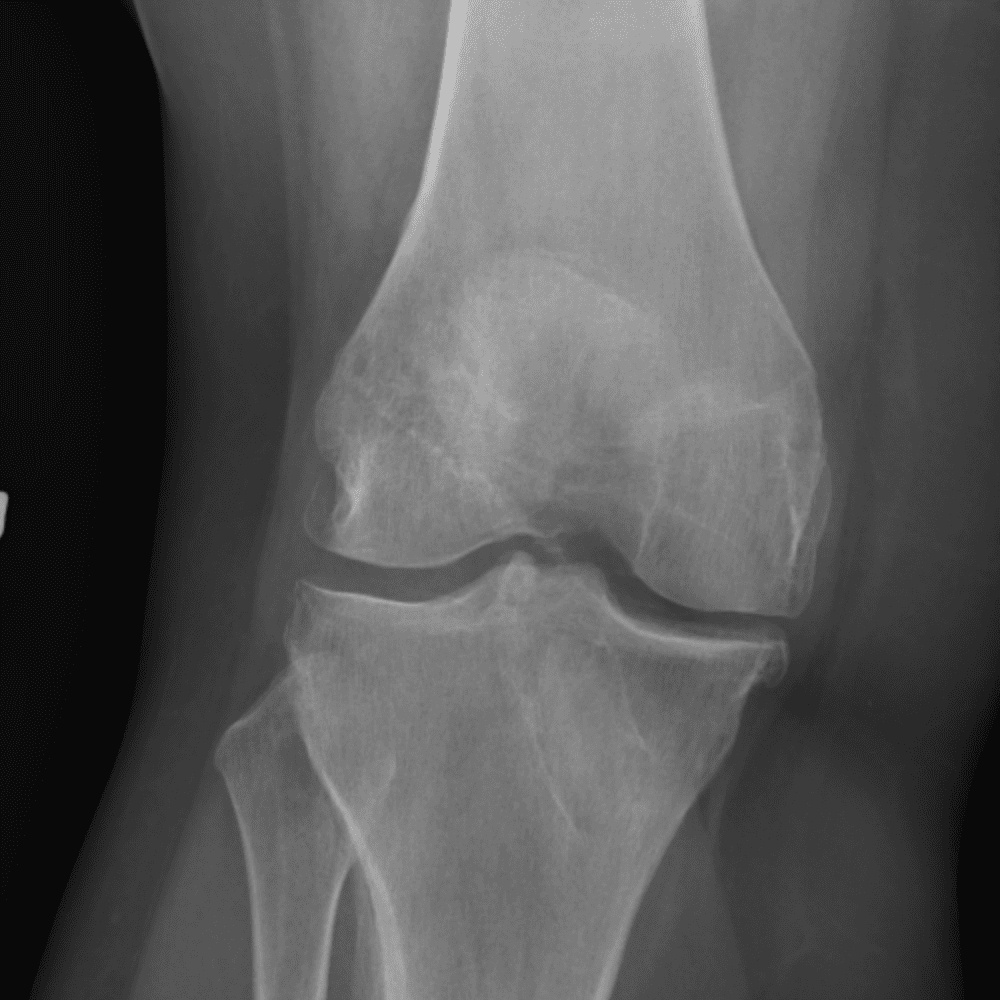

Simula o plantão incluindo casos sutis ou difíceis e alguns normais.